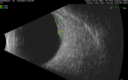

51 year old female with metastatic breast cancer to her bone and brain. She was told about a month ago that there were tumors in her eye. Her vision in the right eye has been declining for a few weeks. VA 20/63 OD, 20/32 OS Her choroidal lesions did not shrink with systemic therapy so in April 2021, she had external beam radiation x 15 sessions and the tumors shrank (4th and 5th set of images)

Bilateral Choroidal Tumors - Metastatic Breast Cancer286 views51 year old female. First 3 sets of images show lesions growing despite systemic chemotherapy. She eventually had external beam radiation x 15 sessions and the tumors shrunk in the last two sets of images00000